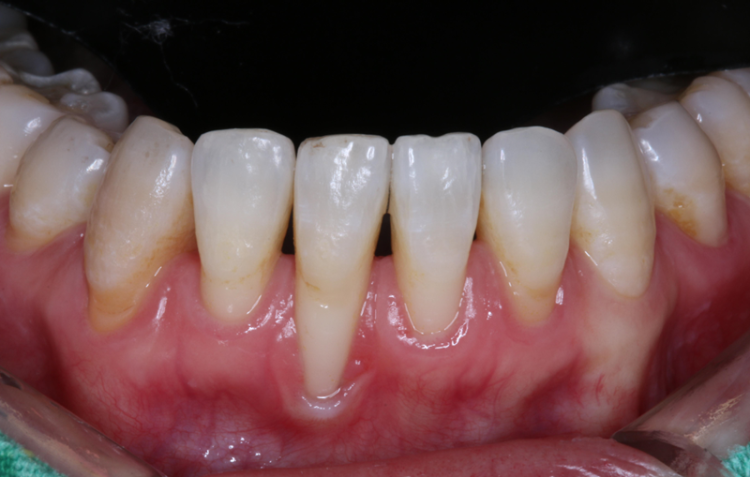

우리가 음식을 섭취하다 보면 구강에는 타액과 세균이 서로 융합이 되면서 플라크라고 하는 얇은 세균 막이 켜켜이 쌓이게 되는데요.

3232235521_53QCocEq_30a7872a49df8f23f856d30079f1f25f96459cc0.png3232235521_CVHQzo9s_b267358bdb708003317b9f202741d2ce0e3bd5d4.png 이때 이 플라크가 제대로 제거되지 않고 음식물과 섞여 단단하게 굳어지게 되면 쉽게 제거되지 않는 단단한 세균 덩어리로 바뀌게 되는데 이를 치석이라고 합니다.

3232235521_PKI0URTs_d1245836cbcb1f0b2d11c53f6df9b5730297f569.png 또 우리의 치아와 잇몸은 완전히 밀착되어 있는 구조가 아니라 치은 열구라고 하는 미세한 틈이 있는데요

만약 치석이 제거되지 않았을 경우에 치석은 이 틈을 빠르게 파고들고 주위의 반경 2mm의 잇몸뼈를 녹여버립니다.

이런 현상이 개선되지 않고 계속 반복되면 점점 잇몸 내려앉음이 발생하고 튼튼하게 잇몸뼈를 지지해 주던 잇몸뼈가 녹아내려 치아도 약해지고

심한 경우엔 발치를 하게 되는 것인데요. 이렇게 치석이 깊게 침투한 상태에서 스케일링을 받아도 치아 표면인 겉만 청소가 될 뿐 잇몸 속은 여전히 치석이 가득 차 있어 아무리 양치를 꼼꼼히 해도 잇몸 염증이 낫지 않고 잇몸 내려앉음이 발생하게 되는 겁니다.